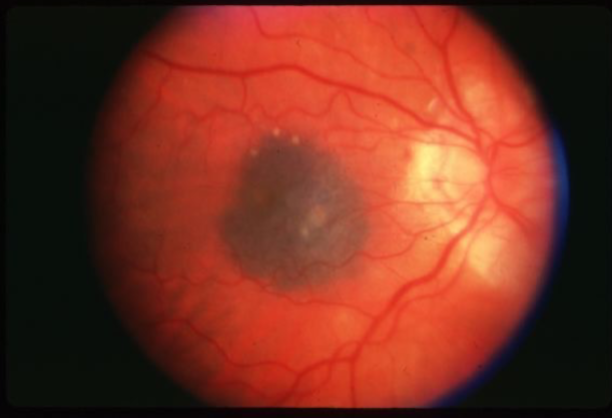

choroidal melanoma

melanoma

melanoma

melanoma

melanoma

melanoma

melanoma

melanoma

melanoma

melanoma

melanoma

melanoma

melanoma

melanoma

melanoma

melanoma

melanoma